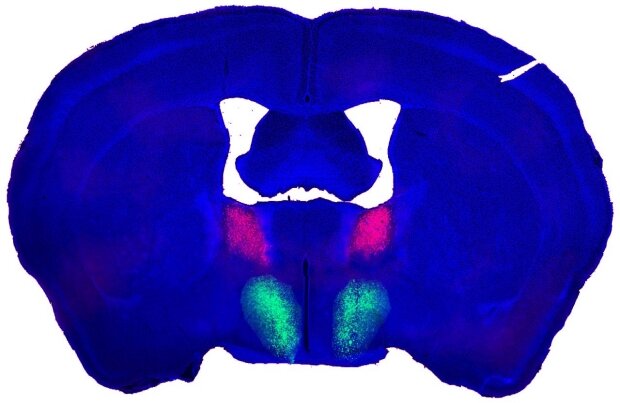

این بررسی بهوسیله پژوهشگران دانشکده پزشکی دانشگاه استنفورد در کالیفرنیا در موشهای آزمایشگاهی نشان داد یک مدار مغزی واحد مستقر برای میل جنسی یا لیبیدوی حیوانات مذکر وجود دارد. این منطقه مغز در موشهای نر دادههای حسی را از محیط دریافت میکند تا جنسیت موش دیگر را شناسایی کند، مثلاً اینکه این موش ماده است و ممکن است تمایل به جفتگیری نشان دهد.

آنها سپس بهدقت سلولهای مغزی و ارتباطاتی را که آنها با این مدار عصبی خاص به نام «منطقه پرهاپتیک هپیوتالاموس »POA) در مغز نقشهبرداری کردند.

این پژوهشگران در بررسیهای قبلیشان در همین مورد دریافته بودند که میتوانند توانایی شناخت موش ماده غریبه بهوسیله موش نر را با دستکاری سلولهای عصبی که از بخشی از مغز به نام بادامک (آمیگدال) در ارتباط با POA خاموش و روشن کنند. بادامک یا آمیگدال در مغز درواقع مرکز ایجاد هیجانات و عواطف است. این پیامهای خاص از بخشی از بادامک به نام «هسته پایینی نوار انتهایی» (BNST) صادر میشود. این کار بهوسیله گروهی از سلولهای عصبی انجام میشود که یک واسطه عصبی به نام «ماده P» را آزاد میکنند که بر گیرندههای مربوط در سلولهای عصبی در POA تأثیر میگذارد و فعالیت آنها را برای یک دوره تقریباً ۹۰ ثانیهای فعال میکند و پس از یک زمان تأخیری ۱۰ تا ۱۵ دقیقهای توالی کامل رفتارهای جفتگیری موش نر شروع میشود.